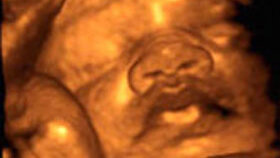

Ультразвуковое исследование во время беременности — это не просто «фото малыша», а важнейшая часть ведения беременности, позволяющая врачу контролировать состояние женщины и развитие плода. На каждом этапе беременности цели и задачи УЗИ меняются: от диагностики факта беременности до оценки готовности к родам. Давайте рассмотрим, какие УЗИ делают в разные стадии беременности, и почему это важно как для врача, так и для самой будущей мамы. Обычно первое УЗИ проводят уже с 5-й недели, при задержке менструации...